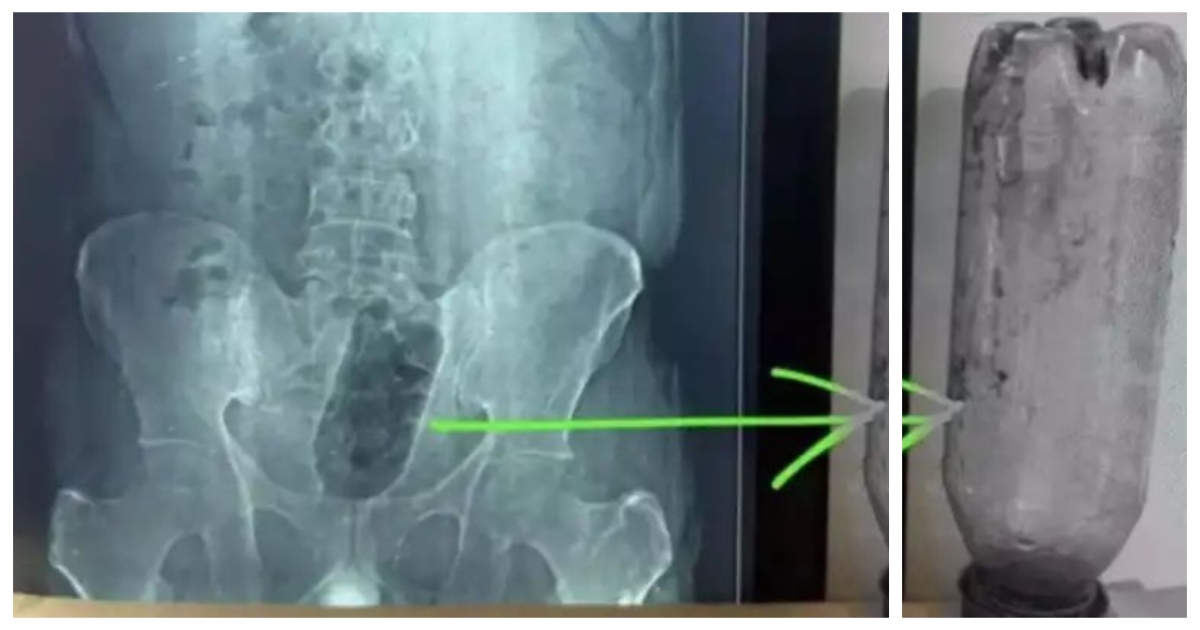

ஆக்ராவின் ஷாகஞ்ச் பகுதியைச் சேர்ந்த சுமார் 38 வயது நபர் ஒருவர் கடும் வயிற்று வலியால் அவதிப்பட்டு மருத்துவமனைக்கு சென்றார். அவருக்கு எக்ஸ்-ரே பரிசோதனை மேற்கொண்ட போது, மருத்துவர்கள் அதிர்ச்சியடைந்தனர். அவரது மலக்குடல் பகுதியில் ஒரு லிட்டர் கொள்ளளவு கொண்ட பிளாஸ்டிக் தண்ணீர் பாட்டில் சிக்கியிருப்பது கண்டறியப்பட்டது.

மூத்த அறுவை சிகிச்சை நிபுணர் டாக்டர் சுனில் சர்மா தலைமையிலான மருத்துவ குழு சுமார் 1 மணி நேரம் 10 நிமிடங்கள் போராடி பாட்டிலை வெற்றிகரமாக அகற்றினர். பாட்டில் நீண்ட நேரம் உள்ளே இருந்ததால் மலக்குடல் பகுதியில் காயங்கள் ஏற்பட்டிருந்ததாகவும் மருத்துவர்கள் தெரிவித்தனர். பின்னர் நான்கு நாட்கள் தீவிர கண்காணிப்பில் வைத்த பிறகு அவர் குணமடைந்து வீடு திரும்பினார்.